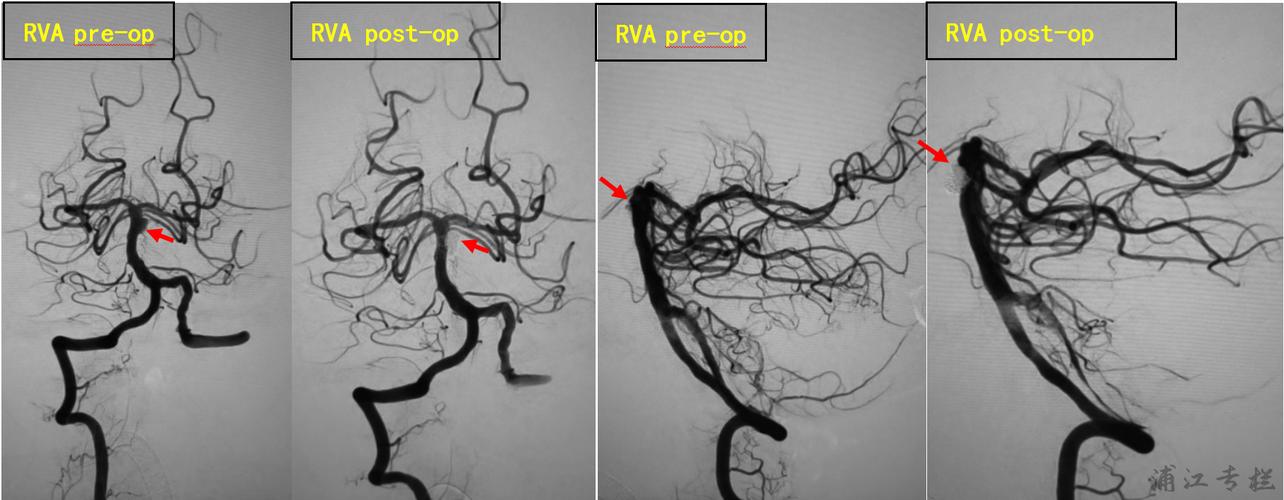

双侧椎动脉造影均显示夹层动脉瘤栓塞完全,基底动脉管腔通畅.